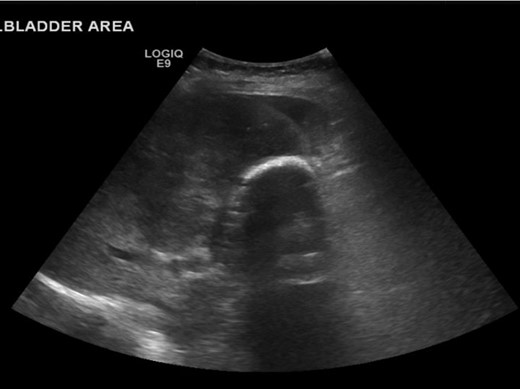

On the current admission, general examination was unremarkable and vital signs were normal. Abdominal examination revealed no organomegaly or palpable mass. Blood tests showed deranged liver function tests (ALT 45 U/l, ALP 775 U/l, total bilirubin 20umol/l, albumin 27 g/l, GGT 553 U/l), hypercalcaemia (adjusted calcium 2.73 mmol/l) and leukocytosis (WCC 10.8 × 109/l). US showed the gallbladder had poor delineation of the posterior wall and appeared large, solid and heterogenous with posterior dense shadowing and with calcific components. Where visualized, the CBD was of normal calibre and no intrahepatic duct dilatation was seen. There was a large, ill-defined heterogenous mass within the liver (Fig. 1). Subsequent computerized tomography (CT) showed a10cm solid porcelain gallbladder invading liver segments 4 and 5 (Fig. 2), with evidence of enlarged coeliac, peri-pancreatic and para-aortic lymph nodes as well as pulmonary metastatic deposits (T4 N1 M1).

US showing porcelain gallbladder with a posterior acoustic shadow.